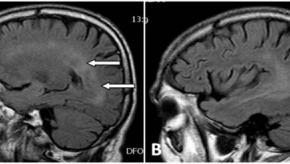

Read ArticleNeurologic Events with TNF Inhibitor Therapy

Demyelinating disorders are an uncommon complication of TNF inhibition and have been described with all TNF inhibitors but also with other biologics.